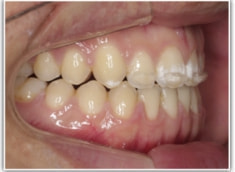

開咬(かいこう:オープンバイト)ケース

治療法:表の矯正(T21ブラケット)

(インプラントアンカーや外科矯正は行わず、エラスティックと機能訓練のみ)

治療後(2年2ヶ月後)